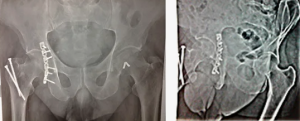

Так, при поступлении пациента с переломом вертлужной впадины и дислокацией головки бедра необходимо в экстренном порядке вправить вывих с последующим наложением скелетной тяги или аппарата наружной фиксации (АНФ), что в дальнейшем облегчит выполнение операции (рис. 1).

При переломах вертлужной впадины, ассоциированных с повреждением тазового кольца (трансацетабулярной нестабильности таза) в первую очередь следует выполнить стабильный внутренний остеосинтез тазового кольца (рис. 4). Восстановление целостности и правильных взаимоотношений отдельных его частей создает прочное основание для прецизионной репозиции и остеосинтеза вертлужной впадины.